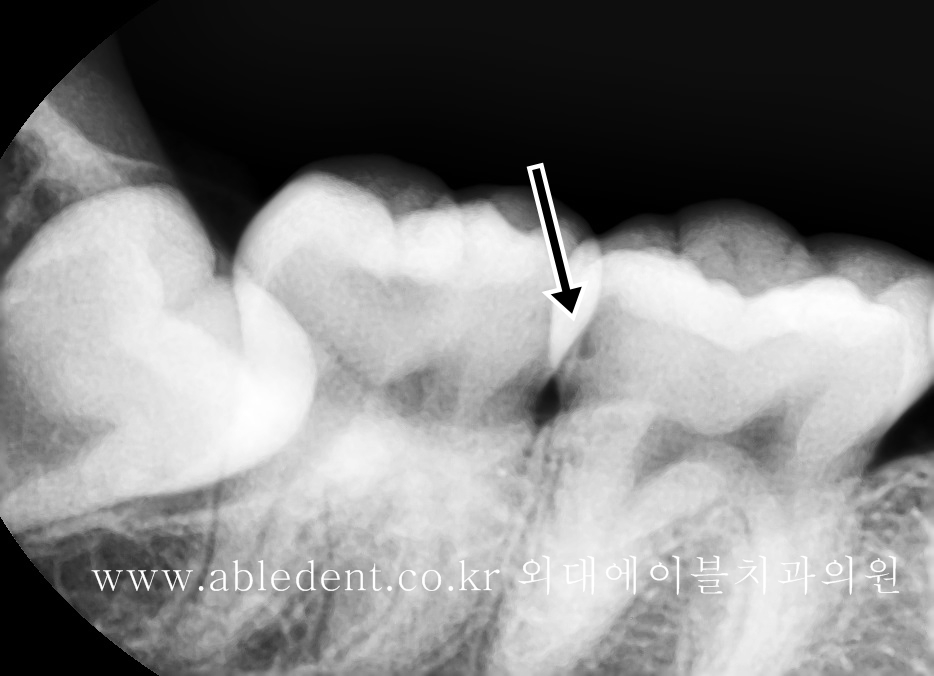

치료에 앞서, 정확한 진단을 위해 치료 전 X-ray 촬영을 통해 정확한 치아의 상태를 파악합니다.

동대문구 이문동에 위치한 저희 에이블치과에서는

모든 충치 치료 전, 반드시 작은 엑스레이를 촬영하여 정확한 진단과 상태 파악을 하고 있는데요.

작은 엑스레이를 촬영하는 이유는, 인접한 충치의 진행 정도, 그리고 교합면 충치의 깊이 등을 알 수 있기 때문입니다.

이 환자분의 경우 X-ray 상에서도 인접한 충치가 확인되고 (덴틴을 넘어서는 것이 확인되고)

교합면 충치의 경우 신경 가까이까지 깊이 진행되고 있는 것을 알 수 있었습니다.